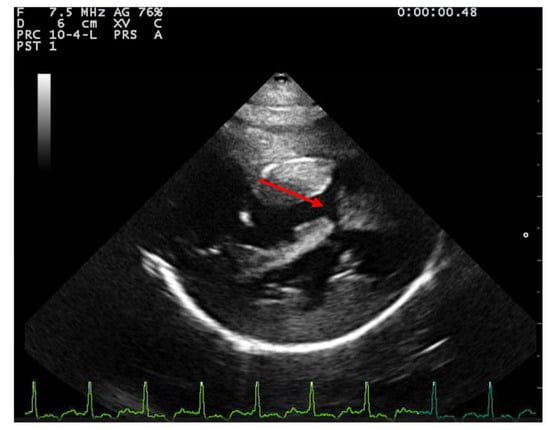

Figure 1.

Right parasternal long axis view from a 2-year-3-month-old domestic shorthair neutered male cat. A large ventricular septal defect can be observed (red arrow); the tricuspid valve is severely thickened (blue arrow). Severe hypertrophy of the right ventricular free wall, moderate hypertrophy of the left ventricular wall, and right atrial dilation are present. RVFW—right ventricular free wall, IVS—interventricular septum, LVFW—left ventricular free wall, RA—right atrium, LA—left atrium.